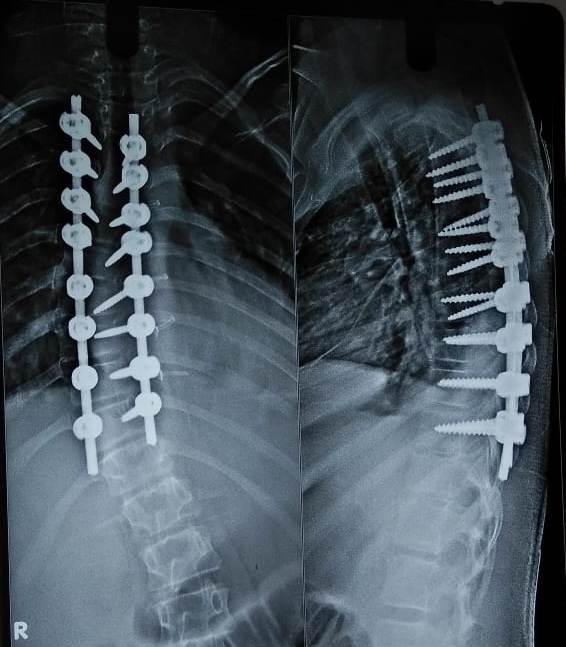

SCOLIOSIS SURGERY

cervical

Scoliosis Patient before Surgery

Scoliosis Patient After Surgery